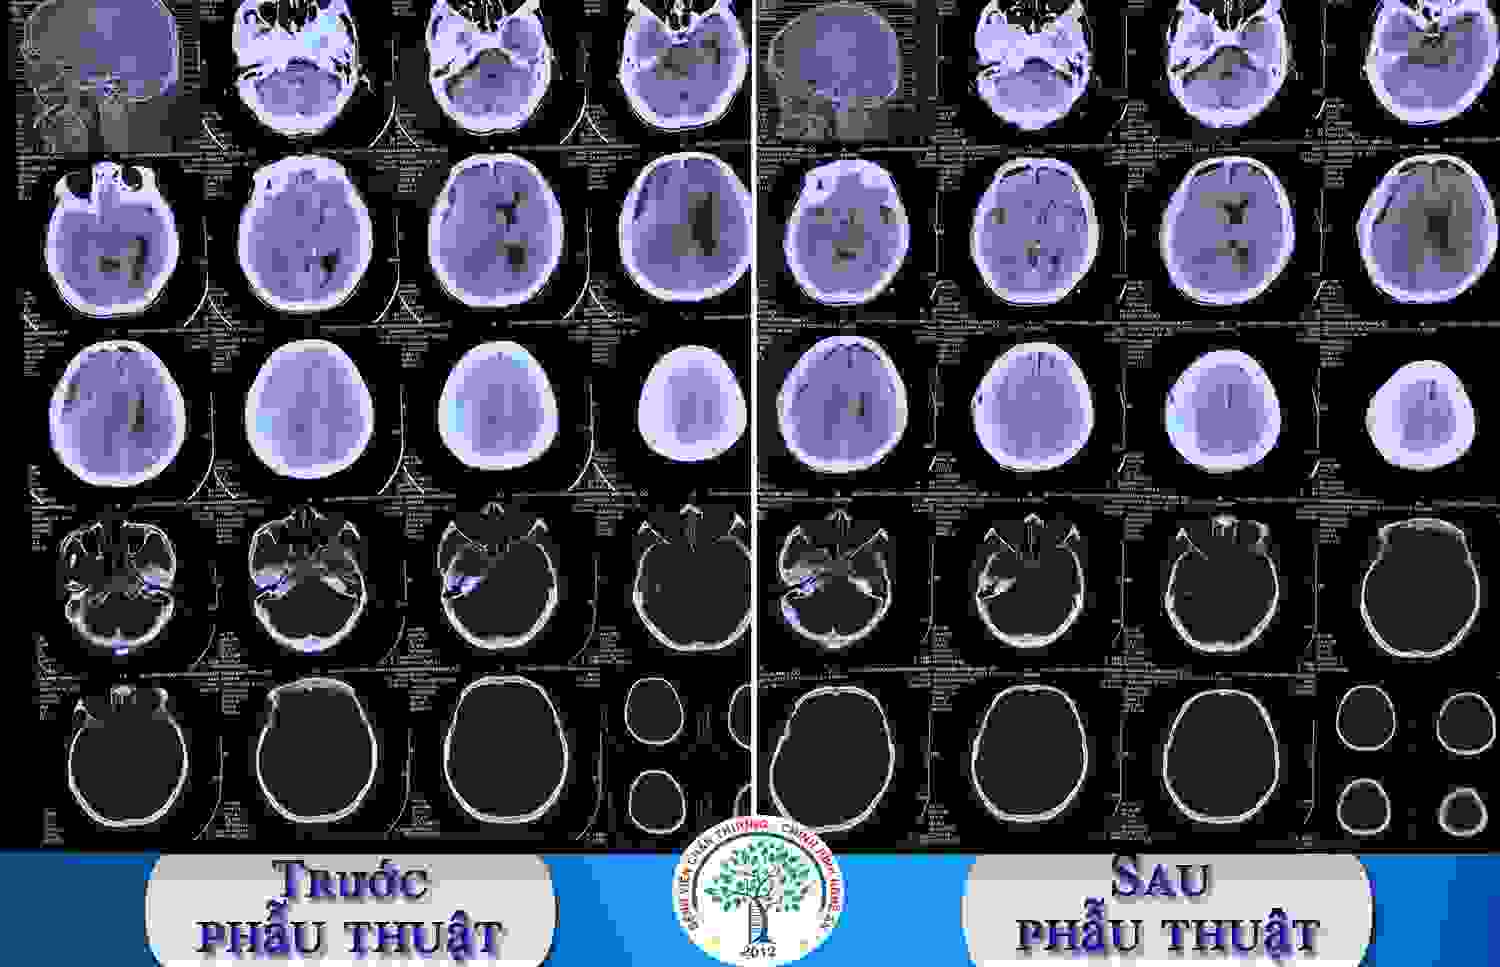

SKĐS - Bệnh viện Chấn thương Chỉnh hình Nghệ An triển khai thường quy phẫu thuật nội soi cột sống với vết mổ nhỏ, ít đau, mất máu ít, hồi phục nhanh. Kỹ thuật ít xâm lấn này giúp lấy trọn khối thoát vị, bảo tồn cấu trúc cột sống, đảm bảo an toàn, thẩm mỹ, giúp người bệnh sớm trở lại sinh hoạt bình thường.